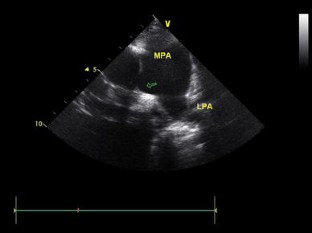

Takayasu’s Arteritis Mimicking Unilateral Pulmonary Artery Agenesis in a Child With Severe Pulmonary Hypertension and Right Heart Failure: A Diagnostic Dilemma

Affliction of the pulmonary arteries in Takayasu’s arteritis is uncommon. Moreover the incidence of pulmonary artery involvement in this condition is often underestimated because of asymptomatic nature in most patients. Severe involvement may however present with pulmonary artery hypertension and hemoptysis, which may prove to be fatal. This case report describes a 9-year-old girl with severe pulmonary hypertension and right heart failure secondary to total occlusion of the right pulmonary artery. Detailed clinical examination and computed tomography (CT) angiography confirmed this diagnosis.

Fig. 3

Video 1 Transthoracic echocardiogram in basal short-axis view showing dilated main and left pulmonary arteries with no right pulmonary artery shadow. (WMV 866 kb)